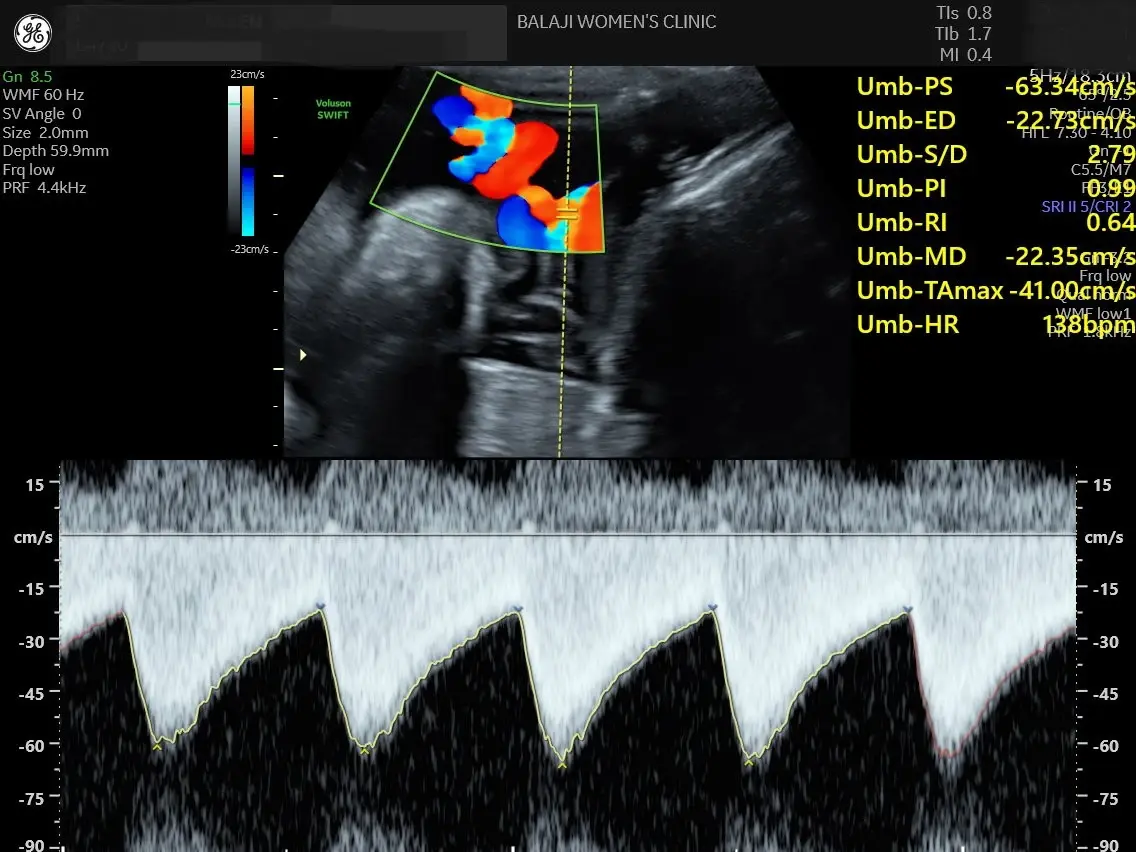

During the scan, doctors analyze the blood flow in important vessels such as the umbilical artery, fetal brain arteries, and uterine arteries. These measurements help determine whether the placenta is functioning properly and whether the baby is receiving adequate blood supply.

Fetal Doppler Ultrasound Scan